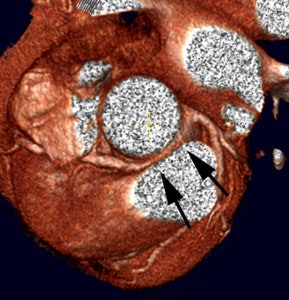

|

Anomalous RCA origin

from the left coronary sinus: The patient below underwent

coronary CT angiography to assess for coronary artery

disease. The patient was found to have an anomalous

RCA arising from the left sinus of valsalva. The

vessel can be seen to course between the pulmonary

trunk and aorta (black arrows) |